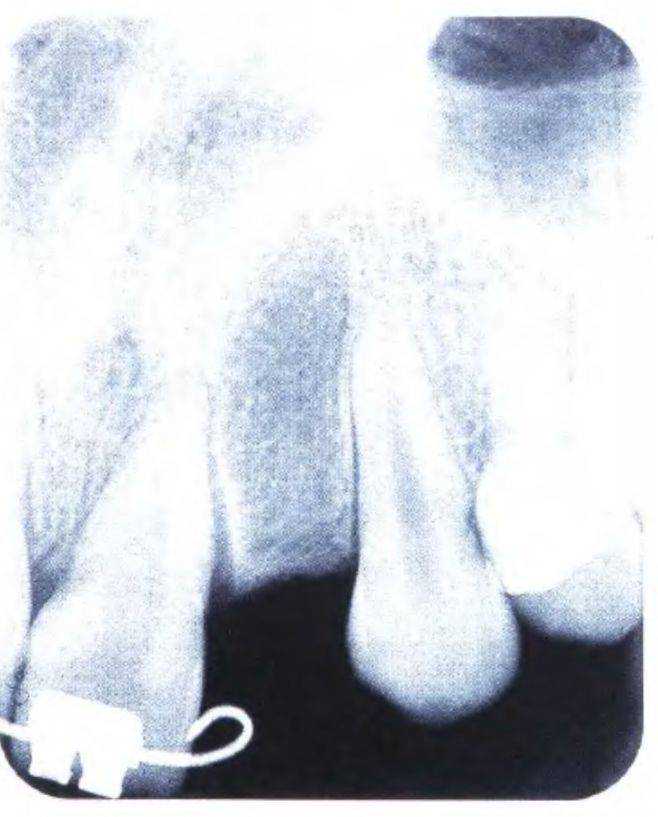

На первом этапе устранили диастему между верхними центральными резцами, чтобы создать пространство в области боковых резцов для установки имплантатов, что выполнили с помощью ортодонтического лечения (рис. с 3-39f по 3-39i). Прицельные рентгенограммы показали достаточное увеличение пространства (рис. 3-39j и 3-39к). Расстояние между верхушками корней можно было увеличить еще больше при использовании ретракционной проволочной дуги с петлями. Следует обсудить с ортодонтом варианты ортодонтического лечения. При проведении рентгенологической диагностики не следует соблюдать рекомендованный производителем оборудования протокол - необходимо подобрать параметры, которые используются при параллельном расположении зуба относительно пленки. Это позволяет полностью отобразить протрузионную и ретрузионную плоскости одновременно. Сотрудники стоматологической клиники, проводящие рентгенологическую диагностику, должны владеть этой методикой.

Рис. 3-39j (слева). Рентгенограмма для оценки пространства в области отсутствующего правого бокового резца

Рис. 3-39к (справа). Рентгенограмма для оценки пространства в области отсутствующего левого бокового резца